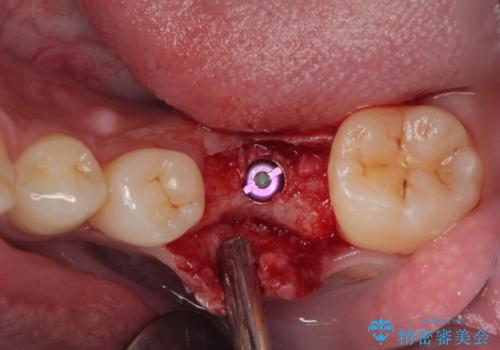

放置した欠損部 奥歯の即時荷重インプラント治療

- 左下欠損部のインプラント治療を希望して来院された患者様です。

左下の欠損部を長期間欠損を放置していたことで、咬み合う上の奥歯が動いてしまっている状態でした。

インプラント部は埋入とともに仮歯を装着し、同時に上顎奥歯の部分矯正を開始することとしました。

理想的な咬み合わせに改善した上で、インプラント補綴治療を行うこととしました。